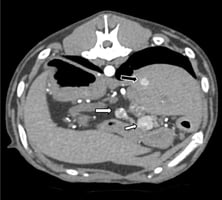

Canine insulinoma: from suspicion to treatment

This article reviews the current evidence and provides a practical, step-by-step approach for clinic...

54 min read